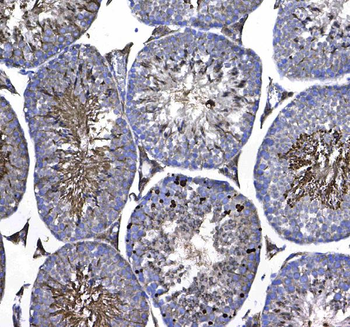

10 μg, 100 μg - Anti-HSPB8/Hsp22 Antibody [orb18992]

FC, ICC, IF, IHC, IP, WB

Human, Mouse, Rat

Rabbit

Polyclonal

Unconjugated

100 μg, 10 μg - Anti-CPI17 alpha/PPP1R14A Antibody [orb19175]